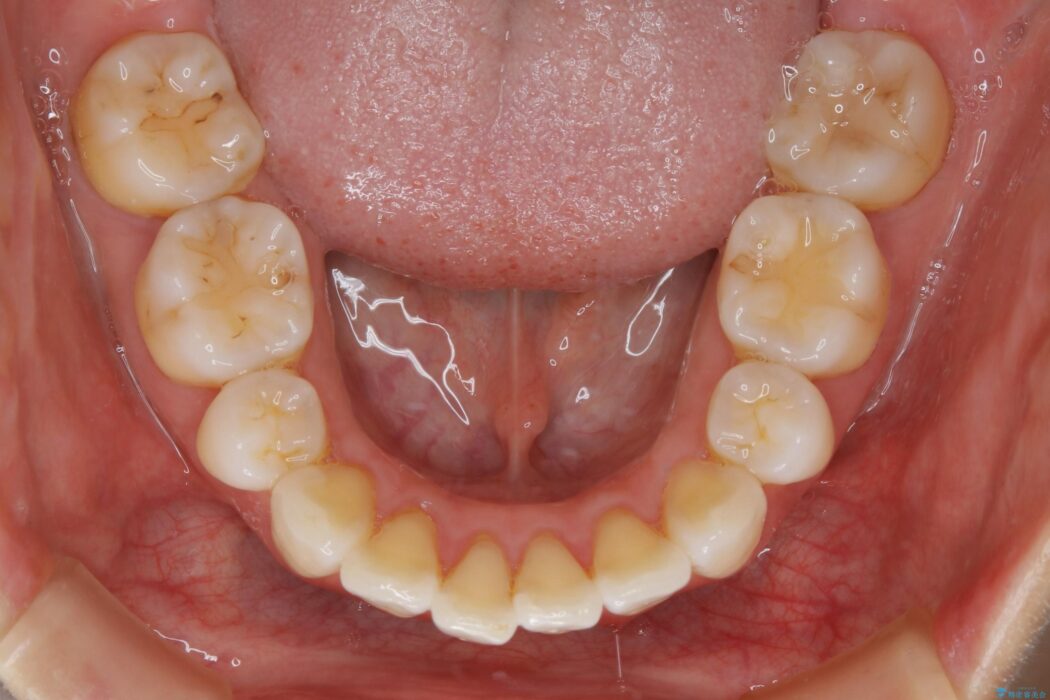

抜歯矯正後の上の前歯の後戻りが気になるとご来院された患者様です。

歯と歯の間を削るのと、歯列のU字型のアーチを僅かに外側に広げる事でスペースを作り、前歯の角度の改善をしました。